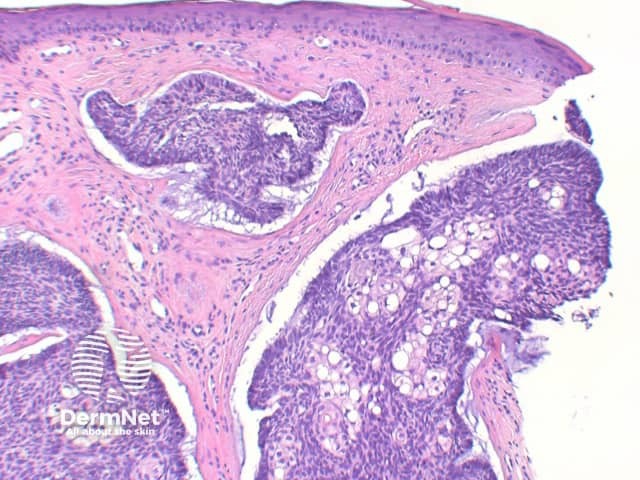

The key feature of basal cell carcinoma at low power magnification is of a basaloid epithelial tumour arising from the epidermis (figure 1). The basaloid epithelium typically forms a palisade with a cleft forming from the adjacent tumour stroma (figure 2). Centrally the nuclei become crowded with scattered mitotic figures and necrotic bodies evident (figure 3). A useful distinguishing feature from other basaloid cutaneous tumours is the presence of a mucinous stroma (figure 4). Some tumours may also show foci of regression, seen as areas of eosinophilic stroma with lack of basaloid nests.

Infundibulocystic BCC: This variant shows multiple small cysts containing cornified material with differentiation towards the infundibulum. In distinguishing from trichoepitholioma, it lacks papillary mesenchymal bodies, but frequently retains a mucinous stroma.